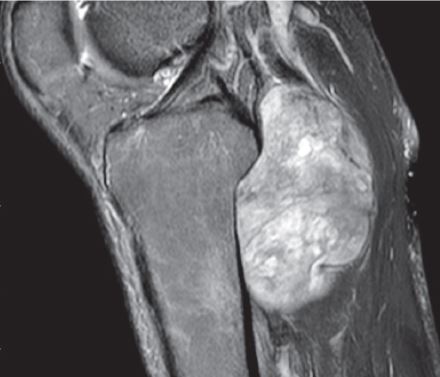

The compartment of the knee involves the tibia, fibula, patella, and distal femur bones. The fibula is a relatively small bone in comparison to the tibia (shin bone) and is a rare anatomic location for both primary and metastatic bone tumors. When a lesion does arise in this area, it typically occurs in the proximal fibula (part of bone closest to knee), followed by the diaphysis (middle part of bone), and finally the distal fibula (lower part of bone near ankle). The most common tumors to arise from the fibula, include chondrosarcoma, osteosarcoma, and benign aggressive cysts. Limb-sparing surgery can be performed for approximately 95% of tumors arising from the fibula. In some instances the extremity cannot be saved and an above the knee amputation is performed.